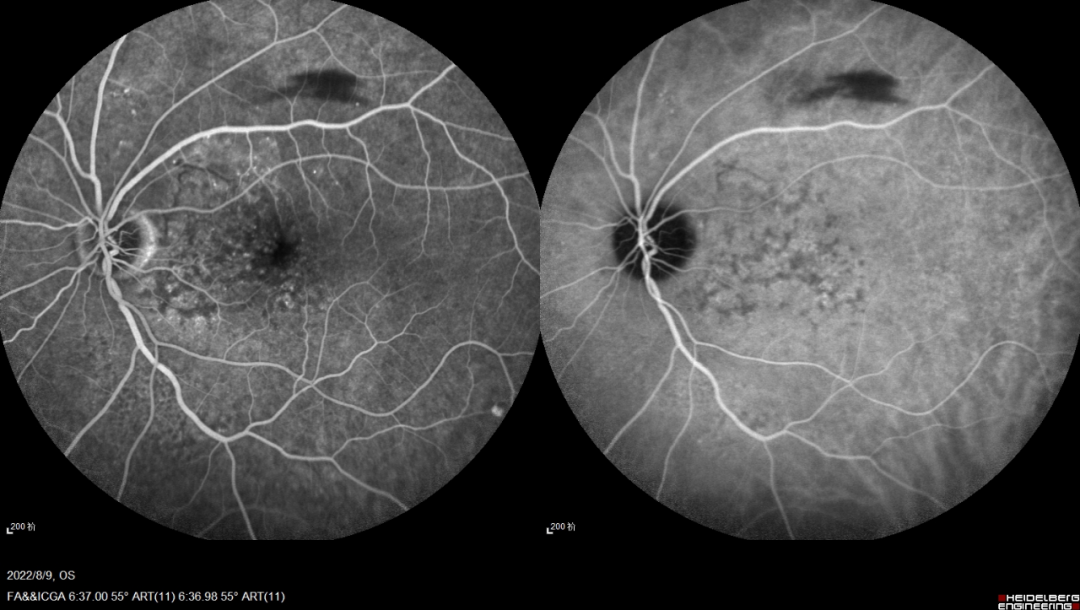

一名21岁的年轻女性,以“双眼视力下降3月余”为主诉就诊,此前已经确诊了SLE ,并且口服激素1年。但其在3月余前无明显诱因出现双眼视力急剧下降,就诊当地医院诊断为“双眼脉络膜炎”,在予药物治疗后无明显好转故就诊于我院。在对其进行眼部体查时可见其右眼裸眼视力为0.25,左眼为0.15,右眼最佳矫正视力为0.8,左眼为0.3。眼底检查双眼视网膜面见大量斑片样脉络膜病灶,自发荧光显示“黑心白边”,病灶围绕视盘,眼底荧光造影显示病灶处有荧光着染,脉络膜造影病灶显示相对应处低荧光。

实验室检查发现,患者除免疫指标存在异常,补体C3、C4水平降低外,T-SPOT检测阳性。结合以上资料,考虑患者为系统性红斑狼疮伴发双眼匍形性结核性脉络膜炎。给予其抗结核治疗以及异烟肼 0.3g Qd、利福平 0.45g Qd等治疗,治疗后患者的眼部情况好转。